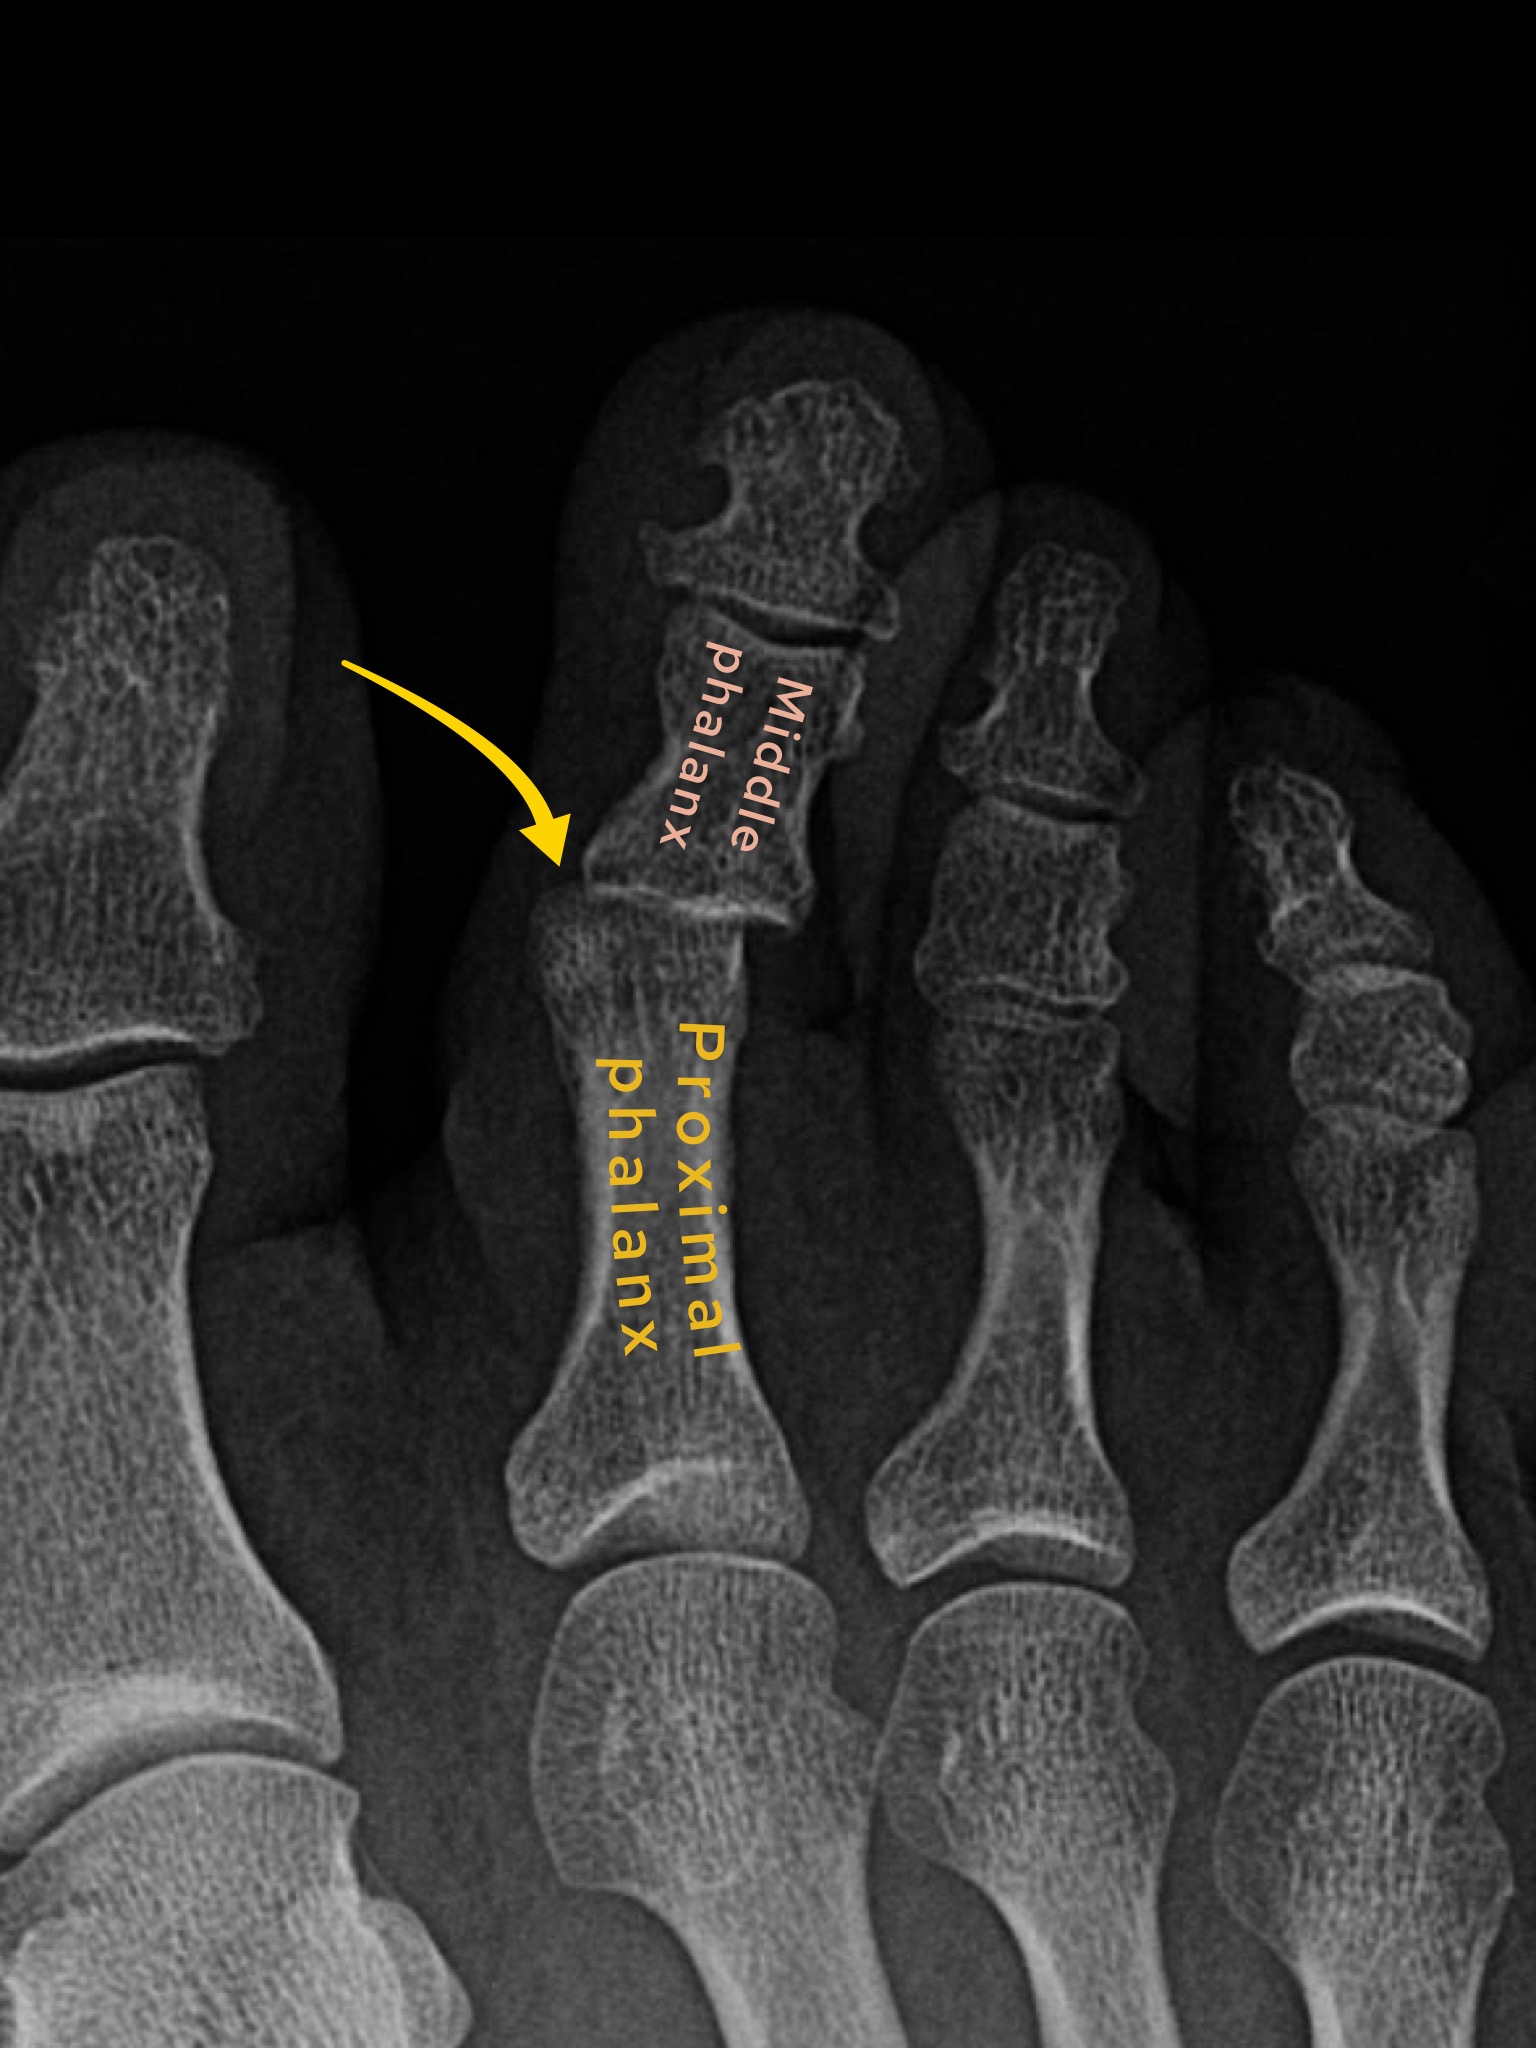

Case 7

A female in her 40s presents to the ED with foot pain after an episode of trauma. What does the foot X-Ray show?

Choose from one of the following: